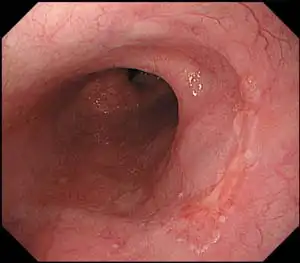

HDTV图像质量提供高清晰度观察功能,即使在一个新的,更薄的范围设计。

这个范围提供了很好的平衡尺寸和性能,HDTV图像质量在一个纤薄的直径8.9毫米的尺寸。